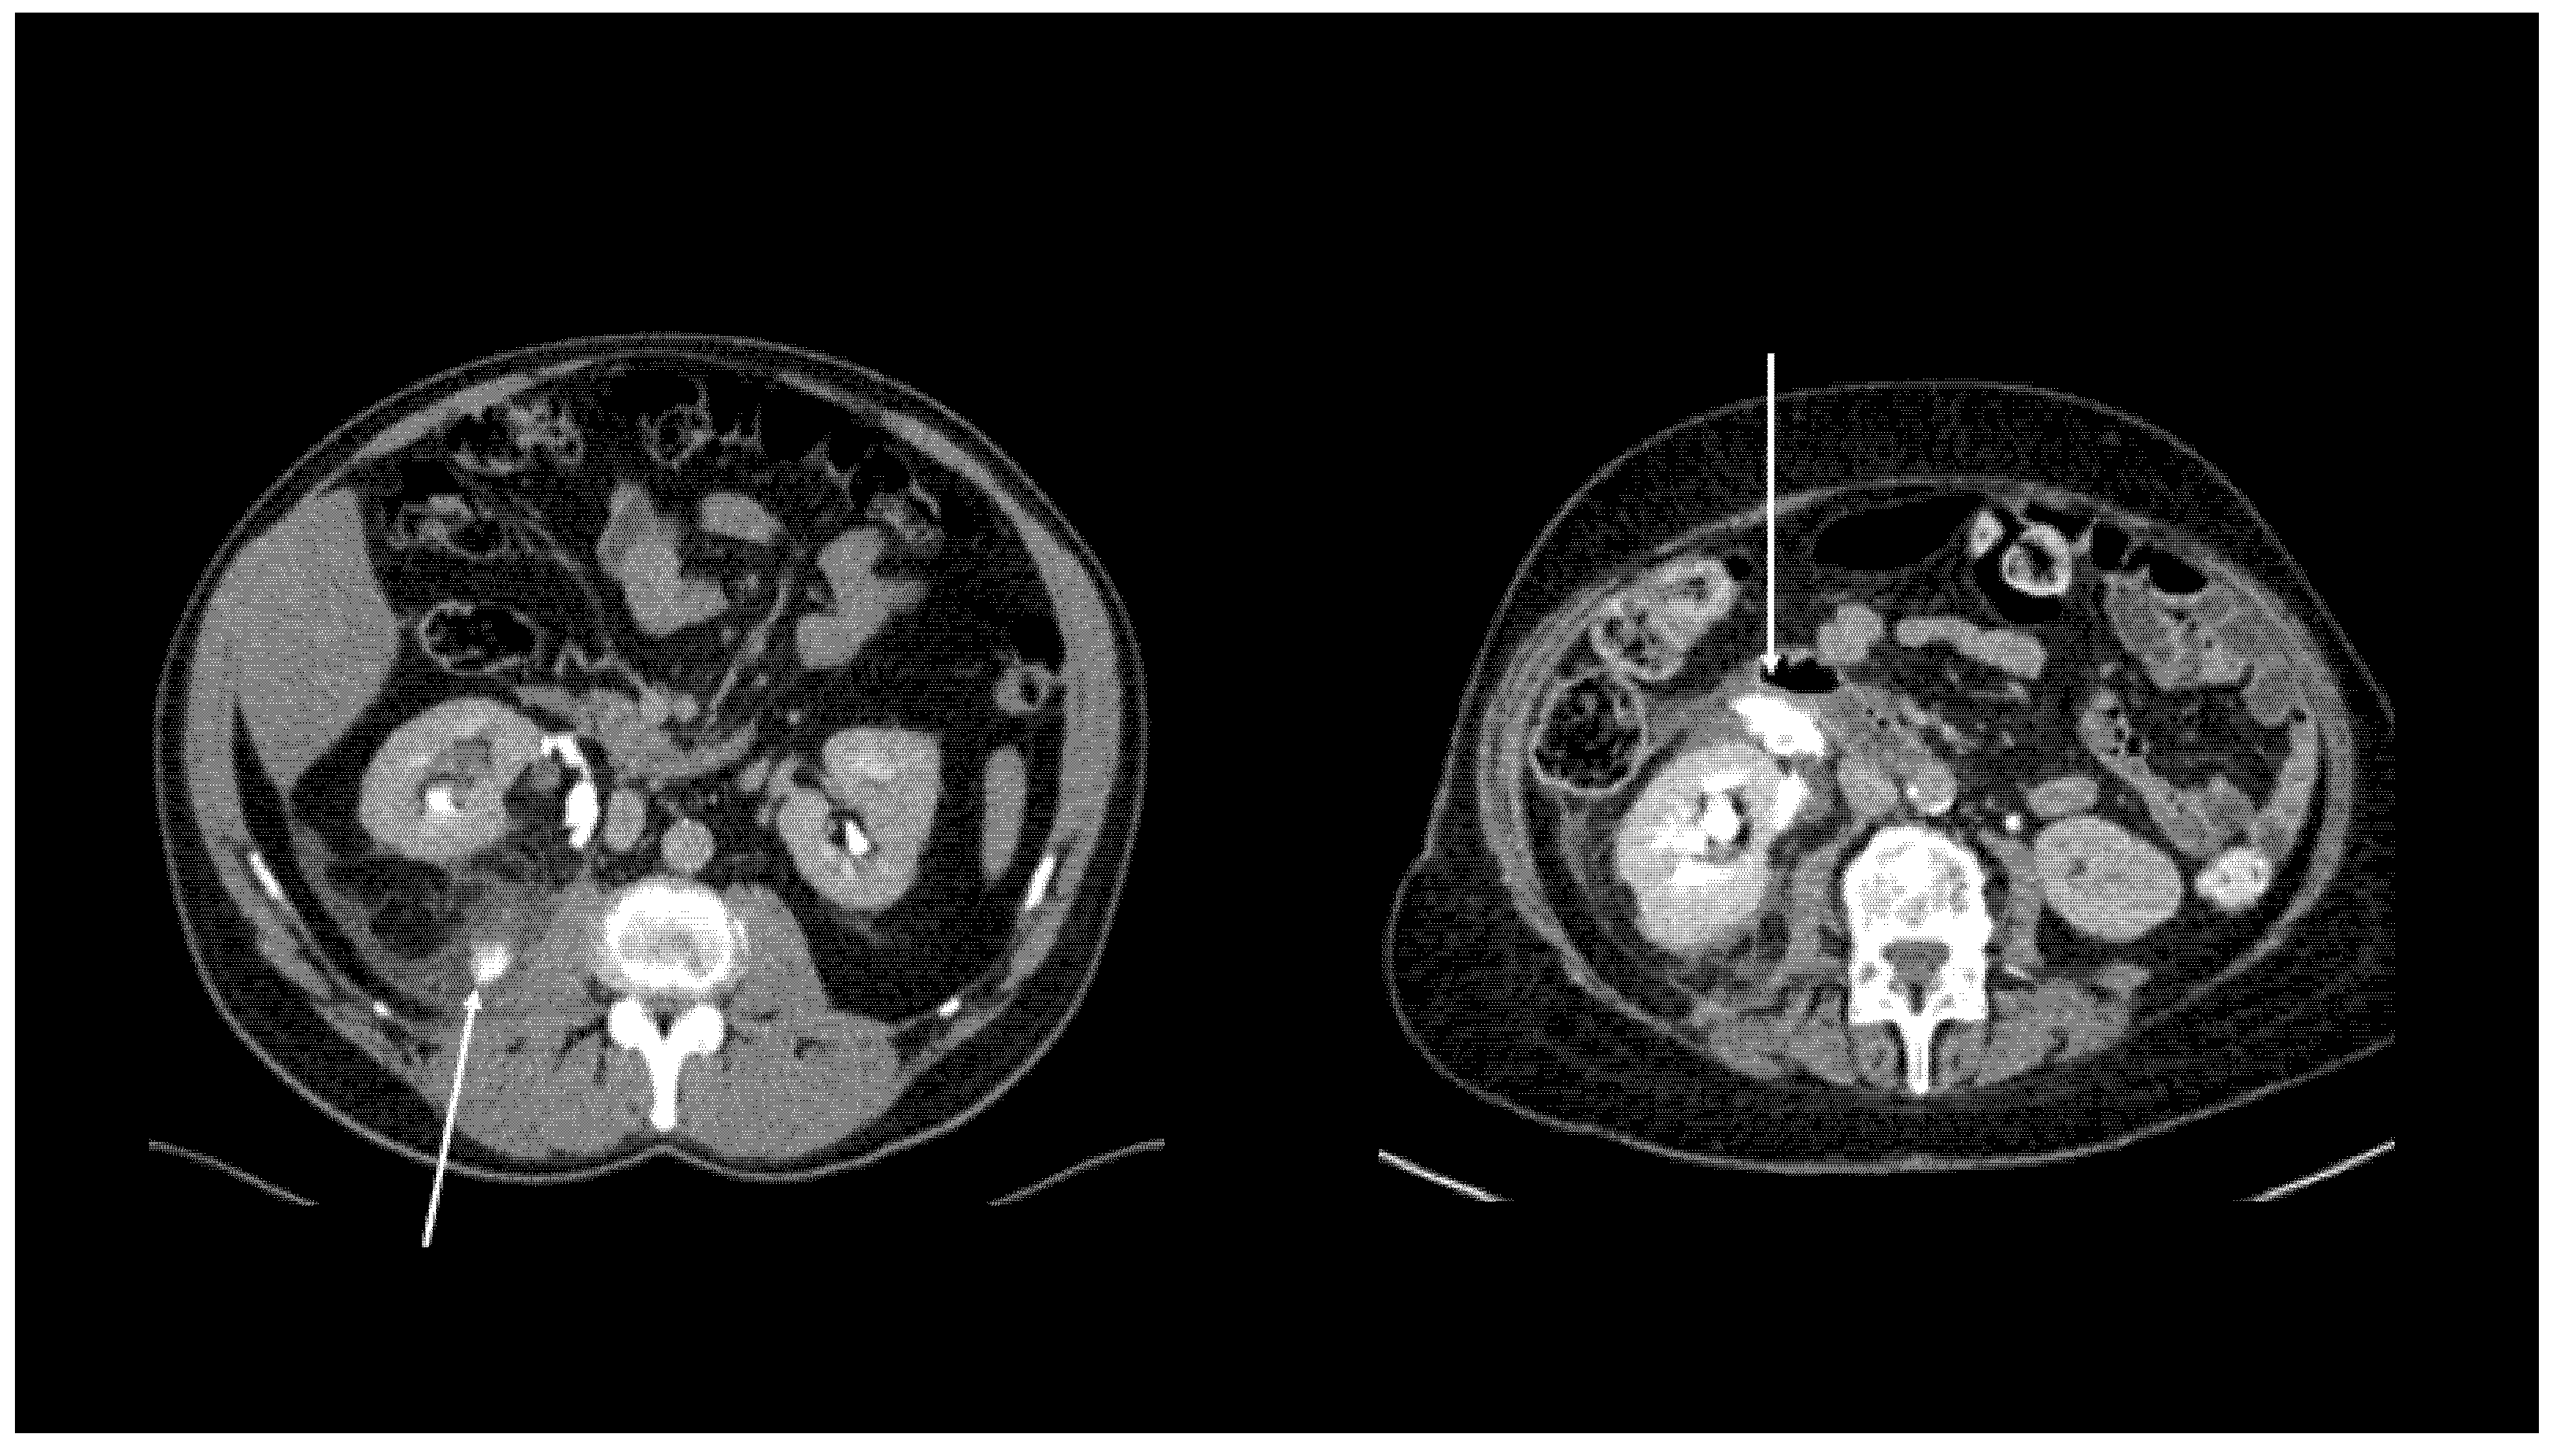

| Local spread | 24 (36.4%) | 27 (40.9%) | 26 (39.4%) |

| Free Fluid | 39 (59.1%) | 36 (54.5%) | 35 (53.0%) |

| Urinoma | 3 (4.5%) | 3 (4.5%) | 5 (7.6%) |

| Cohen’s Kappa | 0.74 * | 0.72 *; 0,70 § | |

| ICC (95% CI) | 0.88 (0.81–0.93) * | 0.87 (0.79–0.92) *; 0.86 (0.78–0.92) § |